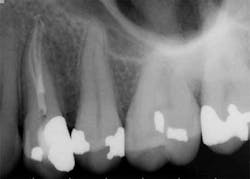

These are my least favorite teeth to treat. Most are heavily restored and the mesial-distal dimension is very small, resulting in no margin for error when locating the pulp chamber. Additionally, there can be significant inclination between the crown and root, and many will have two canals or branching at some level of the canal. (12,15) This lingual inclination of the root results in difficulty obtaining straight-line access into the buccal canal and makes locating the lingual canal almost impossible in some cases, especially if the lingual shelf of dentin is prominent. (Figure 2) Straight-line access into some lingual canals would need to be established through the mid-facial, and this is not a reasonable option for teeth restored with full-coverage crowns. (16)

have two canals. The second canal is lingual

to the main canal, and it is not uncommon for

the two canals to join at the apex. Tooth

No. 24 has a necrotic pulp and based on

the anatomy of teeth Nos. 23 and 26, a

second canal in tooth No. 24 should be expected.